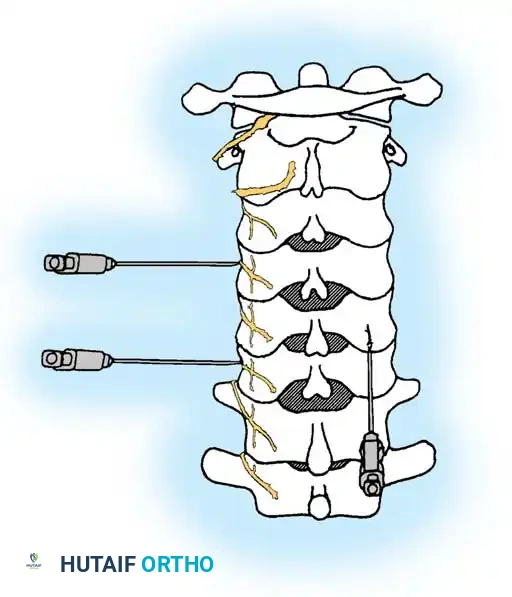

Interlaminar Approach (Technique 39-2)

The interlaminar approach is the gold standard for cervical epidural access. It is routinely performed at the C7-T1 interspace, as the epidural space is widest at this level, minimizing the risk of dural puncture or spinal cord injury. If previous posterior surgery has altered this anatomy, the C6-7 or T1-2 levels are utilized.

5. Needle Insertion: Nick the skin with an 18-gauge hypodermic needle. Under continuous AP fluoroscopic control, advance a 22-gauge, 3 ½-inch spinal needle vertically until contact is made with the upper edge of the T1 lamina, 1 to 2 mm lateral to the midline. Anesthetize the periosteum and soft tissue tract upon withdrawal.

- Tuohy Needle Advancement: Insert an 18-gauge, 3 ½-inch Tuohy epidural needle through the anesthetized tract. Advance vertically until bony contact is made with the T1 lamina.

Transforaminal Approach (Technique 39-3)

Step-by-Step Surgical Technique:

1. Positioning: Place the patient in a modified lateral decubitus position with the symptomatic side facing up. Prepare and drape the lateral neck.

2. Fluoroscopic Orientation: Identify the target neuroforamen. Tilt the C-arm slightly caudad-to-cephalad and anterior-to-posterior to maximize the visualization of the oval neuroforamen.

3. Needle Trajectory: Insert a 25-gauge, 3 ½-inch spinal needle. Advance slowly under live fluoroscopy until contact is made with the lower aspect of the superior articular process.

* Crucial Step: You must stay strictly posterior to the foramen to avoid the vertebral artery, which runs in the anterior aspect of the foramen. Orient the needle bevel notch anteriorly to force the needle tip posteriorly during advancement.

- Foraminal Entry: Redirect the needle to "walk off" the bone into the posterior foramen by 3 to 4 mm. Do not advance further medially than the midpoint of the articular pillar on the AP view.